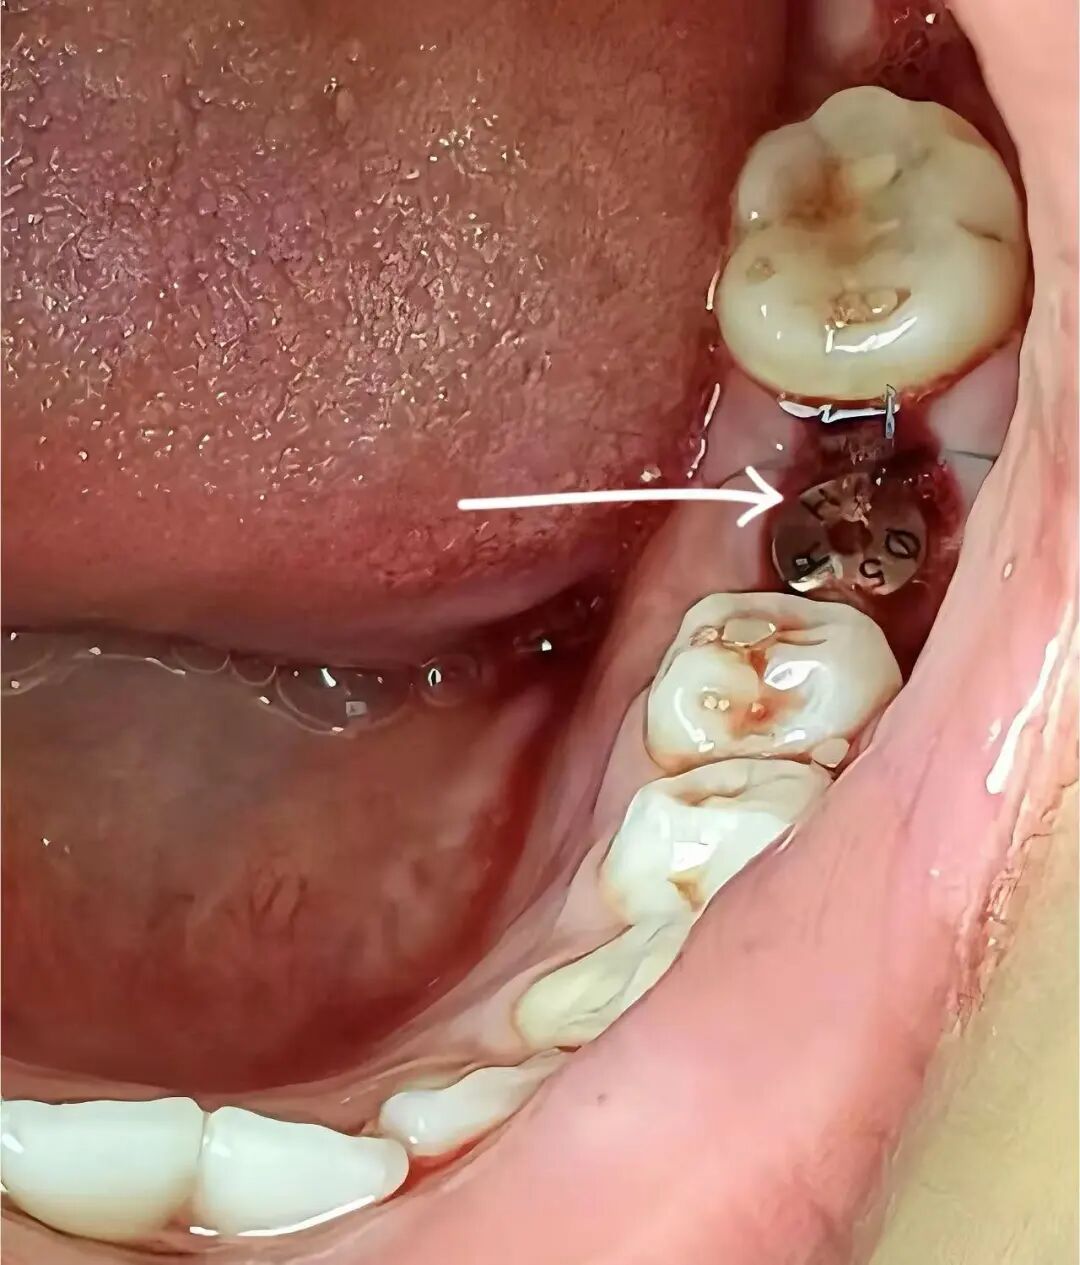

刘大爷深受缺牙困扰多年,在了解了种植牙基本情况后在我院进行了身体检查,随后决定种植牙。张中兴医生为刘大爷进行口腔扫描之后,制定了适合刘大爷的种植牙诊疗方案。在手术过程中张中兴主任精准地切开牙龈,在牙槽骨上制备种植窝。对于种植体植入的角度、深度,张主任有着近乎苛刻的要求,确保种植体能够与牙槽骨完美结合。植入种植体,最后进行种植上端修复。术后3个月,刘大爷来医院复诊,双侧咬合稳定,种植体周围未见异常。刘大爷十分满意,终于能安心品尝美食了。刘大爷感谢道:“多亏了张医生帮我装上了牙,现在吃饭都更香了。”